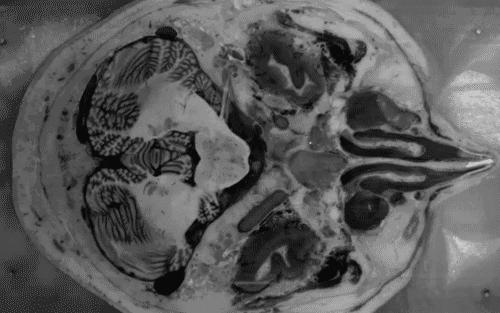

科学研究发现,干细胞能够改善缺血性脑损伤和脑瘫动物模型的运动功能。在杜克大学开展的这项交叉试验中,63名脑瘫患儿被随机安排静脉注射干细胞或安慰剂,并在1年后进行交替注射。治疗1年和2年后,研究人员开展了运动功能和磁共振脑连通性研究。结果发现,适当剂量的干细胞注射可以改善脑瘫儿童的大脑连通性和运动功能。